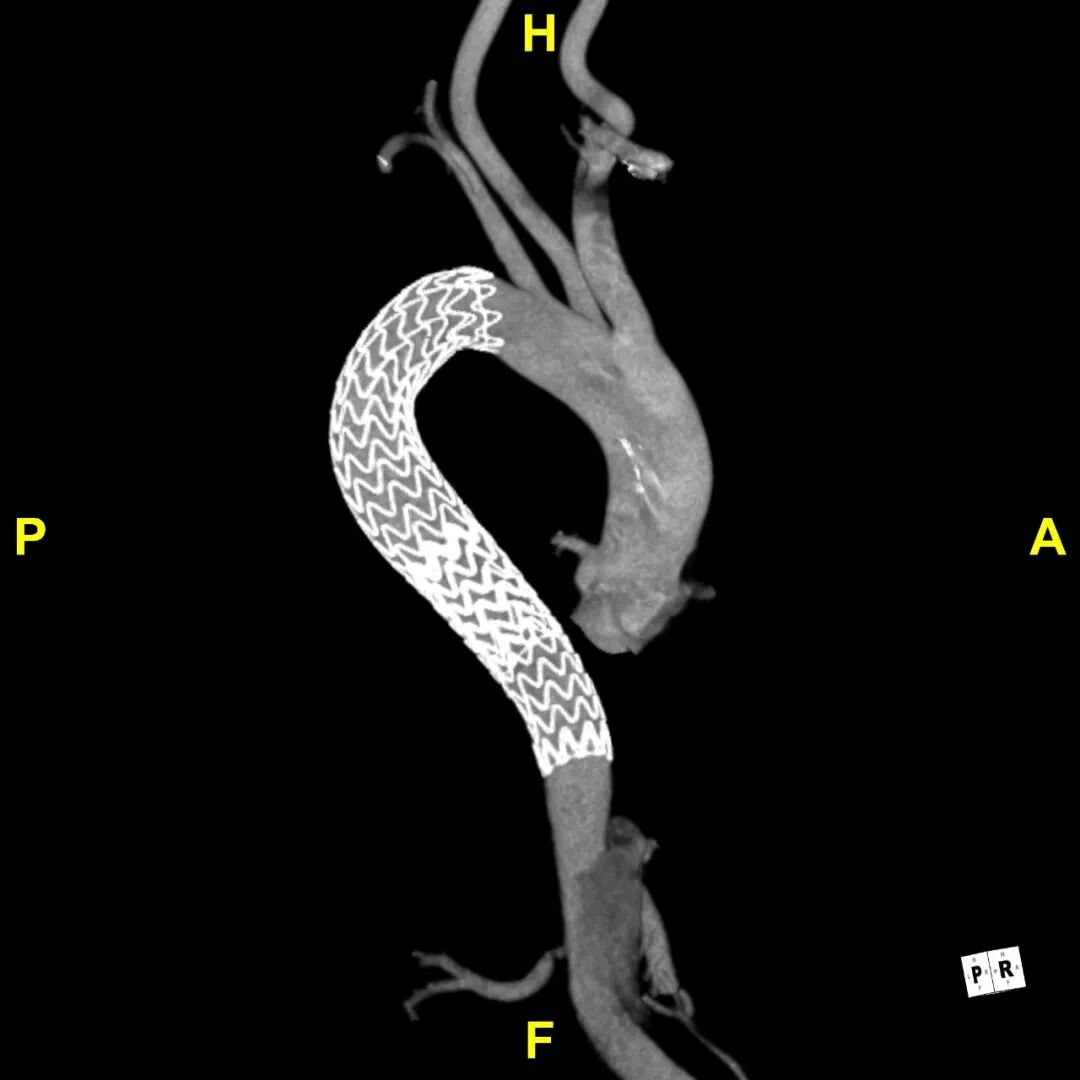

患者出院前进行CTA复查,支架形态良好,与血管壁紧密贴合无内漏,胸主段假腔隔绝,真腔重塑良好。

术后CTA

术后3D重建动态

术后3D重建